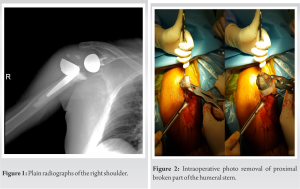

Further evaluation was done with a computed tomography of the right shoulder to evaluate any occult fracture around the shoulder girdle and bony fracture was excluded from the study. A one-stage operation was planned for revision. We used the previous incision line for the deltopectoral approach. After reaching the glenohumeral joint, the prosthesis was found to be dislocated and broken at the humeral tray of proximal stem. The model itself was a modular stem and due to the suspicion of infection, samples were taken from the surrounding synovium and joint fluid. Metallosis and debris tissue were debrided. The humeral stem and the glenoid hemisphere were removed with its cement (Fig. 2 and 3) and a cemented long humeral stem (SMR, Lima LTO, Udine, Italy) was placed (Fig. 4).